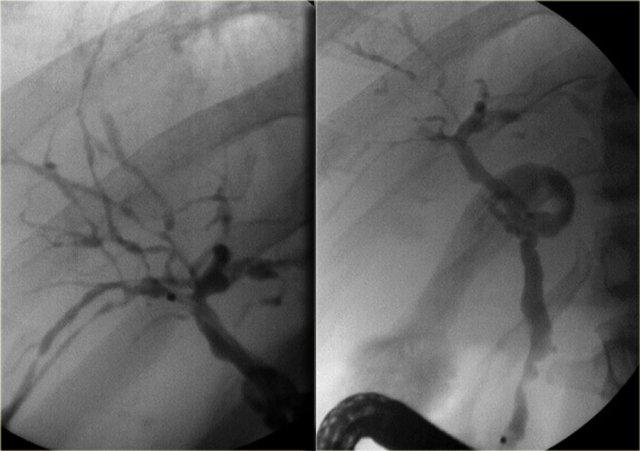

Chụp đường mật được sử dụng trong chẩn đoán ban đầu của bệnh khi chỉ có các chỗ hẹp tinh tế, và ở những bệnh nhân đã biết mắc PSC để tìm kiếm các chỗ hẹp mới nghi ngờ ung thư.

Trên hình ảnh chụp đường mật, chúng ta có thể thấy:

- Hình chuỗi hạt (Beading): hình ảnh xen kẽ giữa các chỗ hẹp và các đoạn ống mật bình thường hoặc giãn nhẹ

- Hình cây trụi lá (Pruned-tree): các ống mật ngoại vi bị hẹp và khó quan sát

- Bờ thành không đều (Mural irregularity): bờ lòng ống không đều (thấy rõ nhất ở bên trái trong ống mật ngoài gan)

- Túi thừa (Diverticula): thấy rõ nhất ở bệnh nhân tiếp theo

Bên trái là các dấu hiệu điển hình trong PSC.

Lưu ý các túi thừa trong hình bên phải.

Túi thừa có tính đặc hiệu rất cao cho chẩn đoán PSC.

Vì vậy, khi phát hiện các túi thừa này, bạn cần tìm kiếm ngay các chỗ hẹp tinh tế ở các ống mật trong gan.